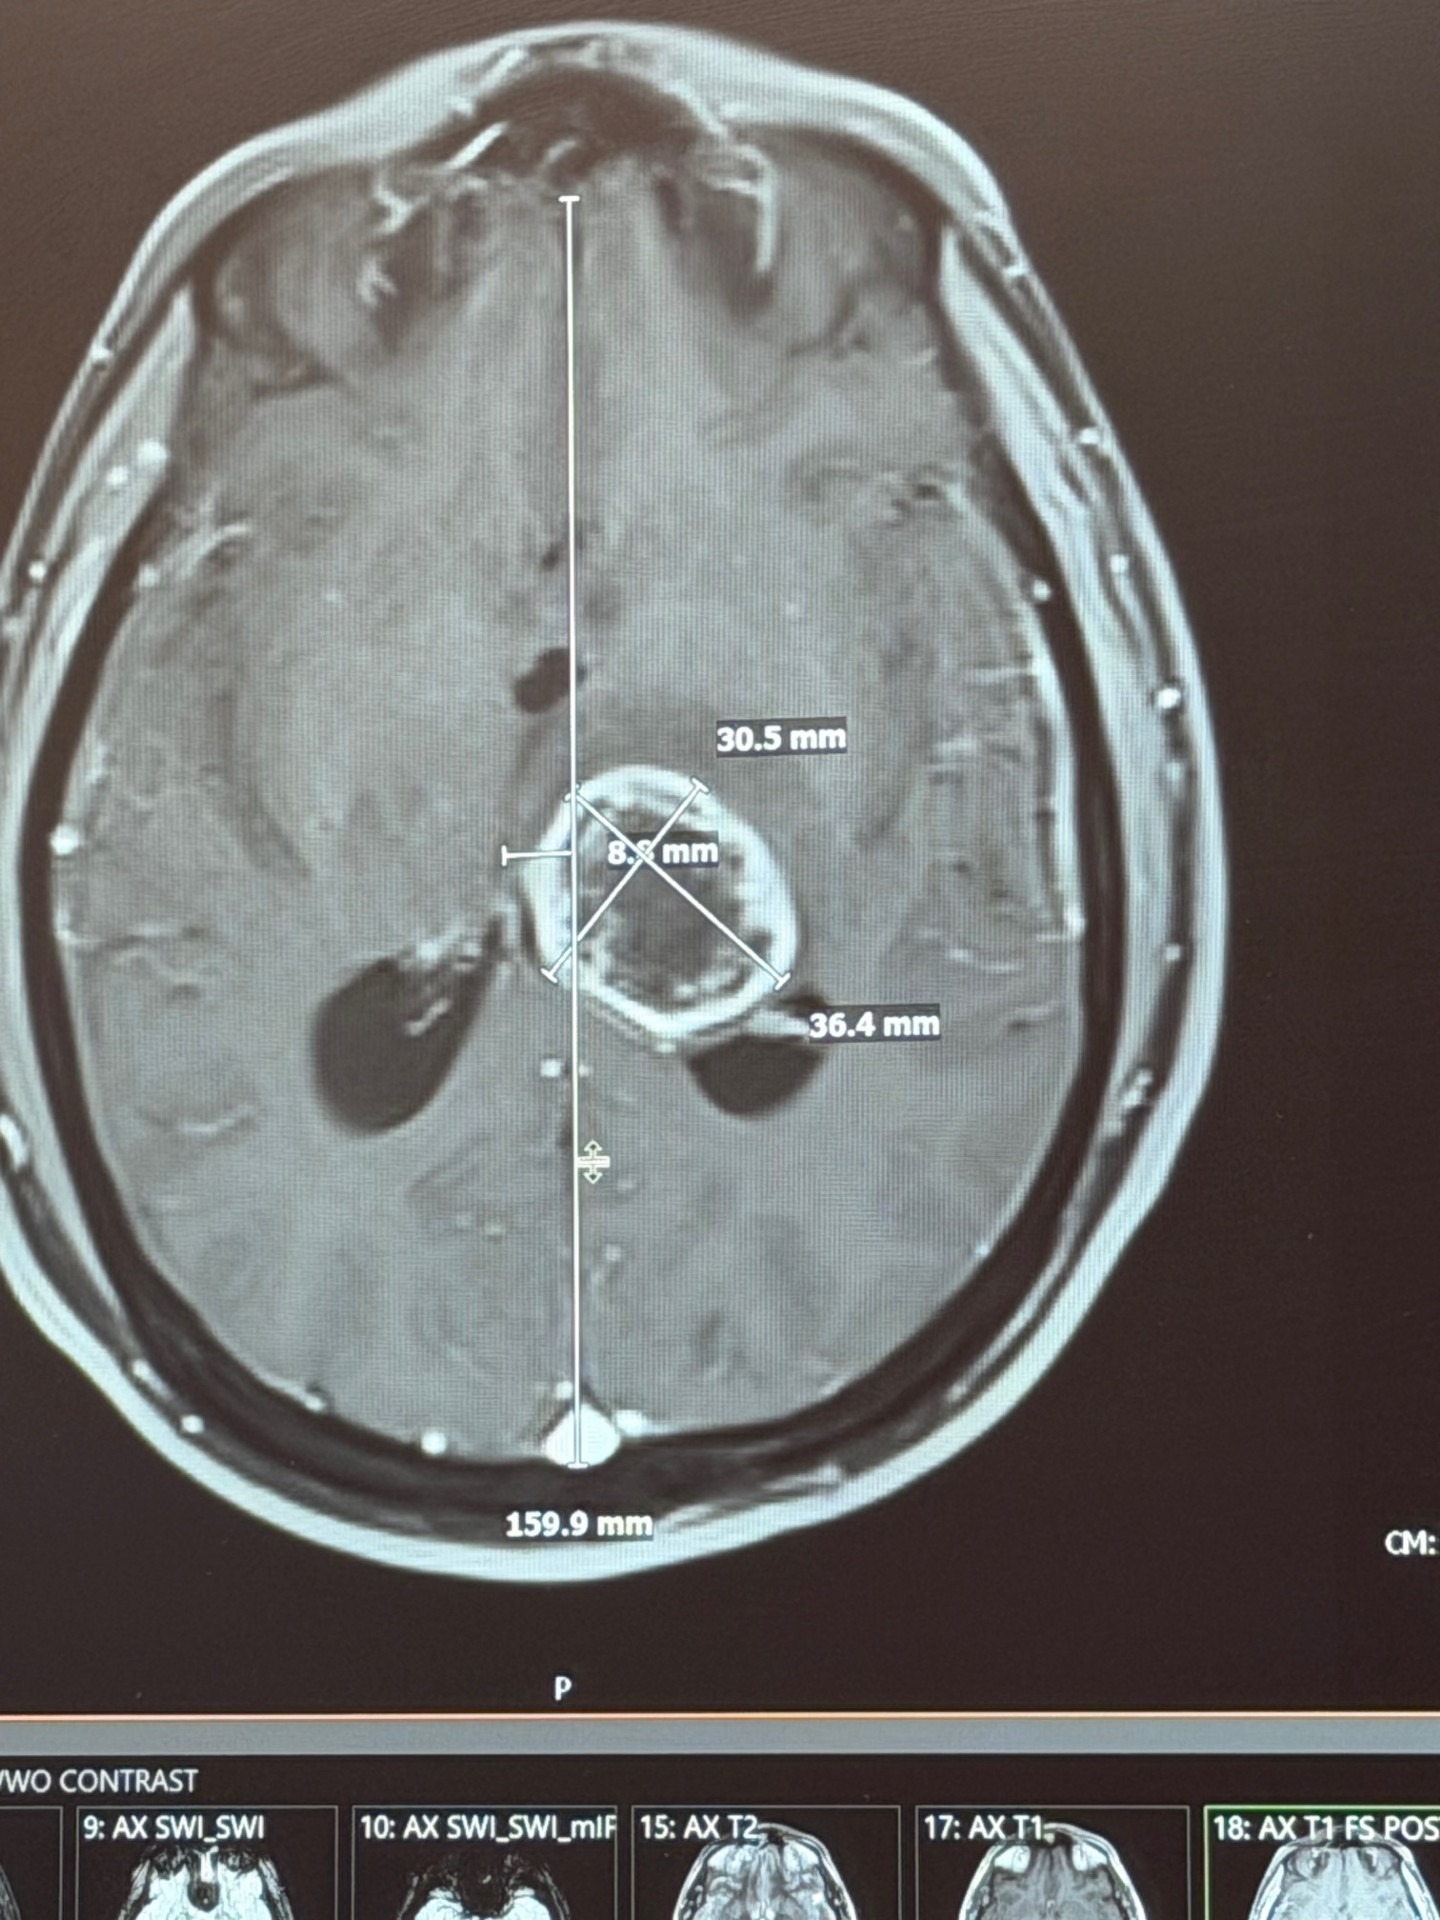

My name is Matthew, and I’m reaching out because I’m facing one of the toughest challenges of my life. I was recently diagnosed with a high-grade glioma in my brain stem. It all started when I went to the hospital with a headache, and after some head scans, the doctors found a mass. A brain biopsy revealed it was very aggressive and required fast, aggressive treatment. Everything changed so quickly, and I’m now preparing for a four-week treatment plan that will be both physically and emotionally demanding.